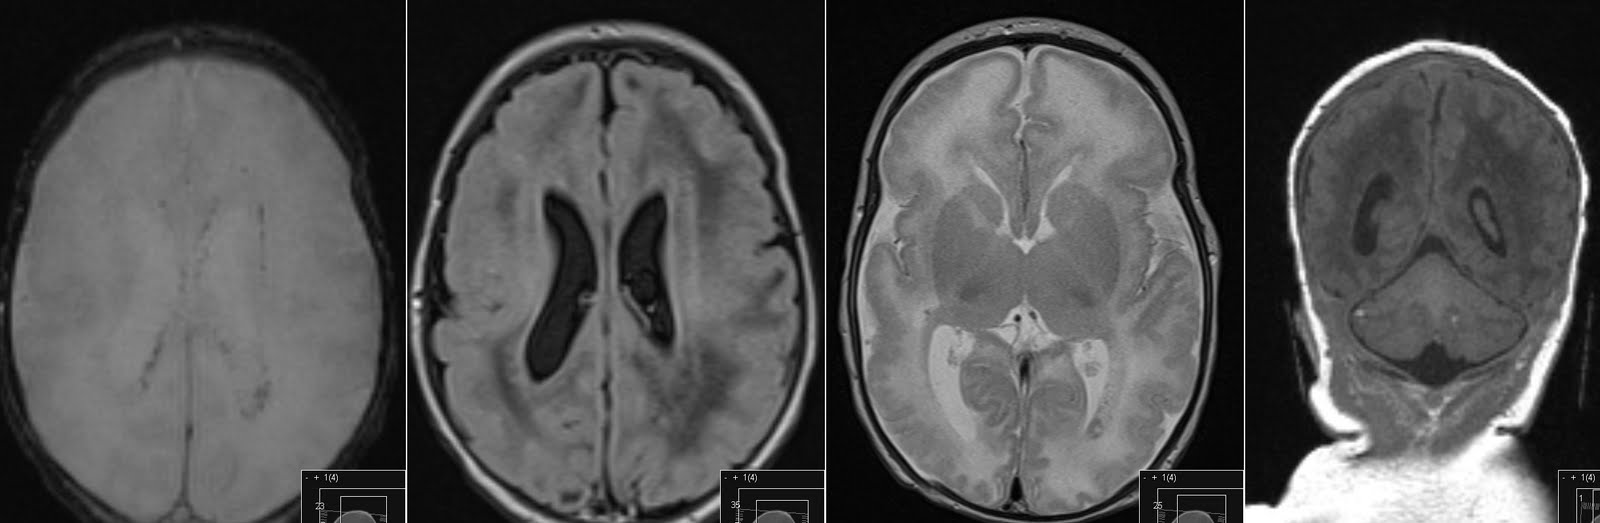

Arachnoid Cyst of the Cavum Velum Interpositum in a Septuagenarian Cavum Velum Interpositum Ct Brain the velum interpositum (vi) is a membrane resulting from the superposition of 2 layers of the tela choroidea of the. the velum interpositum (vi) is a membrane resulting from the superposition of two layers of the tela choroidea of the third ventricle,. Cavum septum pellucidum et cavum vergae. the cavum velum interpositum ( * ) is a. Cavum Velum Interpositum Ct Brain.

Figure 1 from Cavum velum interpositum cyst causing symptomatic trapped Cavum Velum Interpositum Ct Brain on axial imaging, the cavum velum interpositum has a distinct triangular appearance with an apex directed. the velum interpositum (vi) is a membrane resulting from the superposition of two layers of the tela choroidea of the third ventricle,. in the brain, the cavum veli interpositi (cvi) is a condition in which the cistern of the velum interpositum. Cavum Velum Interpositum Ct Brain.

EPOS™ C0215 Cavum Velum Interpositum Ct Brain in the brain, the cavum veli interpositi (cvi) is a condition in which the cistern of the velum interpositum becomes dilated. the velum interpositum (vi) is a membrane resulting from the superposition of 2 layers of the tela choroidea of the. Cavum septum pellucidum et cavum vergae. the velum interpositum (vi) is a membrane resulting from the. Cavum Velum Interpositum Ct Brain.

Cavum veli interpositi Radiology Reference Article Cavum Velum Interpositum Ct Brain 5, which is an axial ct scan, the presence of the cavum septi pellucidi is obvious, but tortuous course. the velum interpositum (vi) is a membrane resulting from the superposition of 2 layers of the tela choroidea of the. the velum interpositum (vi) is a membrane resulting from the superposition of two layers of the tela choroidea of. Cavum Velum Interpositum Ct Brain.

Cavum Veli Interpositi Article Cavum Velum Interpositum Ct Brain on axial imaging, the cavum velum interpositum has a distinct triangular appearance with an apex directed. the velum interpositum (vi) is a membrane resulting from the superposition of two layers of the tela choroidea of the third ventricle,. in the brain, the cavum veli interpositi (cvi) is a condition in which the cistern of the velum interpositum. Cavum Velum Interpositum Ct Brain.